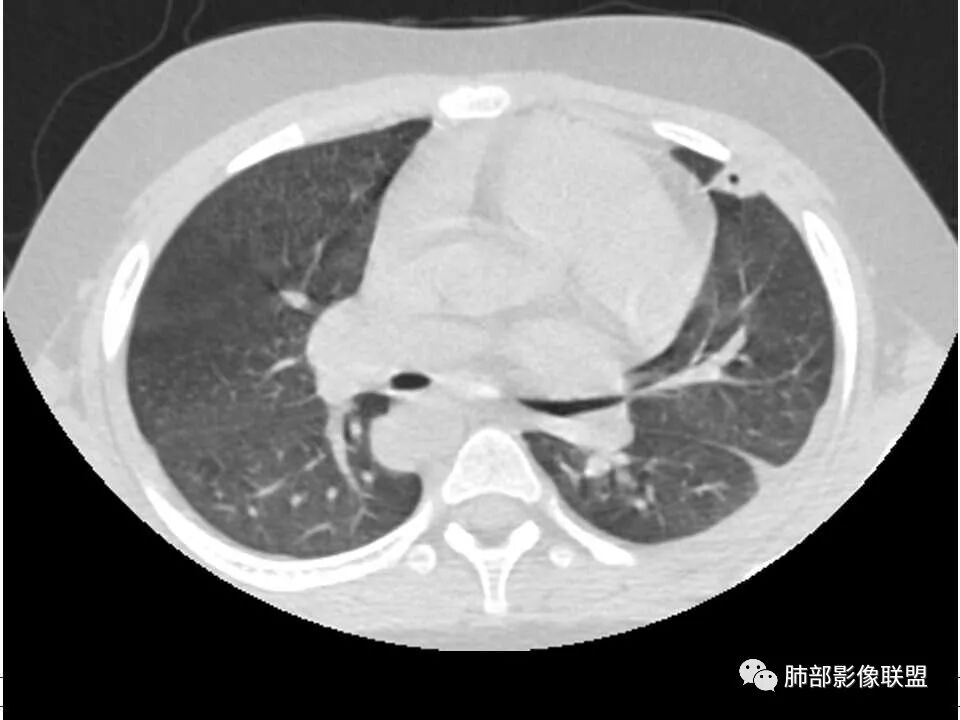

患者儿童,因右下肢疼痛伴肿胀14天就诊。病程中有发热及伴随症状。膝关节MRI提示右侧膝关节及右髌骨髁异常信号影,右膝髌上囊及关节腔内少量积液。胸部CT:双肺胸膜下多发结节影,部分结节空洞形成,且结节周围可见血管集束征。综合考虑血源性脓毒性肺栓塞、坏死性肺炎。右侧骨髓炎、血播性金葡菌肺炎,鉴别其他特殊感染及血管炎。

发热,下肢肿胀骨髓水肿,骨髓炎可能;双肺多发结节,部分空洞,左下肺胸膜下楔形阴影,考虑感染性病变,肺梗死;上腔静脉、奇静脉增宽,肝大,考虑股部深静脉拴子进入体循环及肺动脉,综上考虑下肢骨髓炎,深静脉脓毒栓子,肺部感染并肺栓塞

2.双肺多发片影,随机分布,多空洞或囊腔,胸膜下多楔形影,气道未见受累等等符合脓毒血症影像学表现,尤其是金葡。